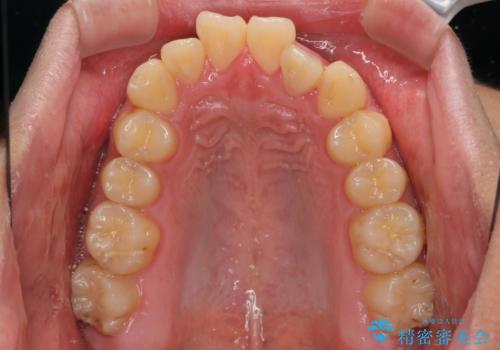

- 前歯のデコボコとクロスバイトを気にして来院された患者様です。

クロスバイトはありましたが、叢生の程度としては酷くなかったため、ワイヤー矯正でもマウスピース矯正でも、好きな方を選択していただきました。

治療開始前は汚れが多く、全体的に歯肉が腫れていましたが、矯正治療を通して腫れも少しずつ改善されました。